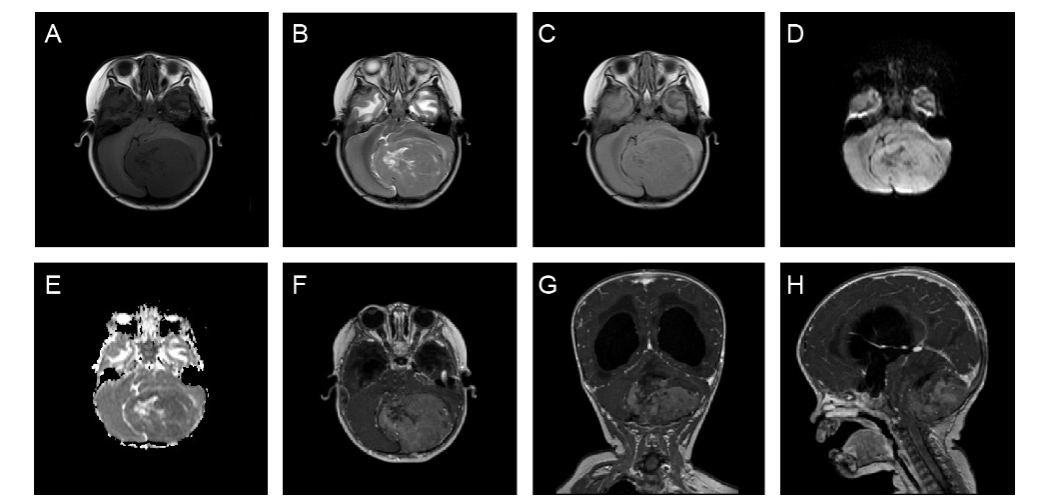

1.小骨窗显微手术:是治疗儿童脑型肺吸虫病的有效方法,具有缩短手术时间,显微镜下顺利寻找病灶边界,减少对周围正常脑组织的牵拉。手术创伤小、恢复周期短,做到对脑组织及周围神经损伤最小。